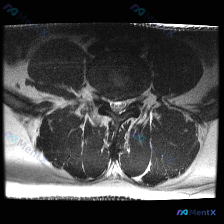

本次提供的是腰椎MRI T2序列轴位图像,分析如下:

- 扫描层面:位于下腰椎节段,可清晰辨认中央的硬膜囊、马尾神经根,以及侧方的关节突关节、椎旁肌肉

- 核心影像发现:

- 椎管形态无明显狭窄,硬膜囊、马尾神经根无明显受压移位

- 椎间盘无明显向后膨出/突出压迫硬膜囊、侧隐窝,椎体后缘平滑无骨赘突入椎管

- 双侧关节突关节间隙清晰,无明显狭窄或增生;黄韧带无增厚钙化,无椎管侵占

- 双侧椎间孔、侧隐窝形态开放,无明显狭窄,神经根走行区无占位压迫

- 椎旁肌肉信号均匀,无水肿、萎缩或脂肪浸润异常